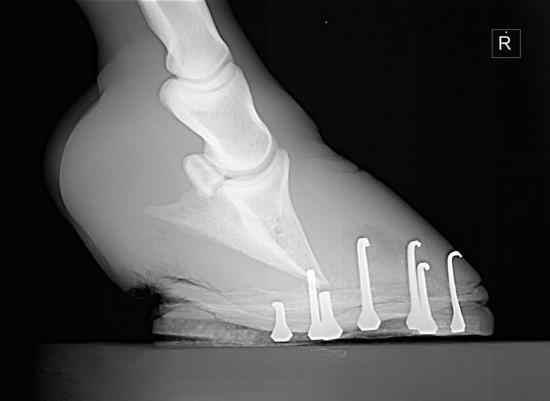

El dolor agudo en los cascos es una señal de alarma máxima. Una actuación rápida es vital para detener el proceso inflamatorio y evitar el hundimiento o rotación del hueso pedal.

Sí. Mi unidad móvil cuenta con radiografía digital y ecografía portátil (entre otros equipos).

Esto me permite, por ejemplo, ver el estado de un cólico (si hay distensión de asas intestinales) o descartar fracturas en caso de un golpe fuerte, todo ello sin mover al caballo de su box.